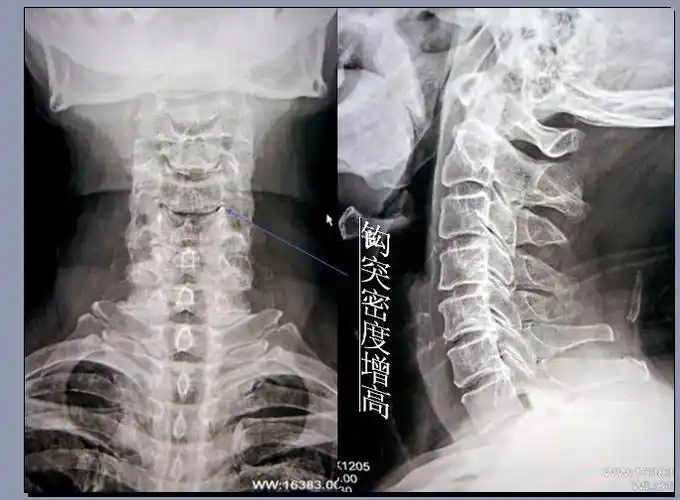

部椎骨主要特征 颈椎 cervical vertebrae 椎体小椎孔大 椎体钩

脊柱解剖 (一).特点 1.颈椎: 棘突分叉 横突孔 椎体钩

展开全部 钩椎关节由第3-7颈椎体上面侧缘的椎体钩与上位椎体的前后

3,钩椎关节

orofinod等人发现,在成人颈椎中,原本存在于钩突与上位椎体间的疏松

刚学会上传 颈椎前面观 上关节突 钩突 下关节突 椎体

看两侧钩椎关节间隙是否相对对称?当急慢性损伤,椎体钩突常出